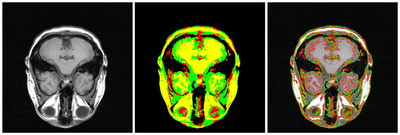

4-phase MRI segmentation